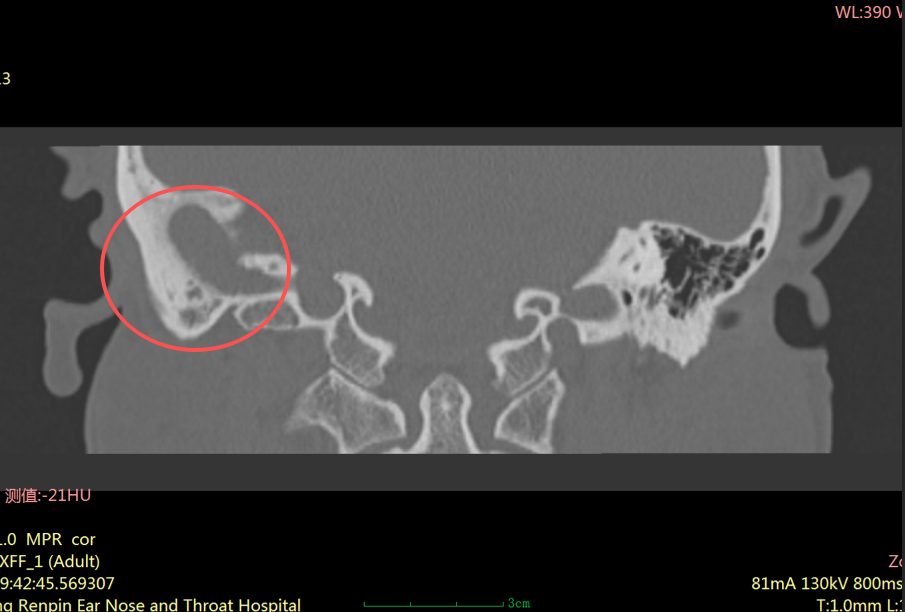

"患者右耳中耳腔已形成胆脂瘤,它像一颗不断侵蚀听骨的‘定时炸弹’,若再拖延,可能引发面瘫、颅内感染等严重并发症。"耳科主任张朝梅指着CT影像解释道。

胆脂瘤并非真正的肿瘤,而是中耳、乳突内形成的角化鳞状上皮堆积物。

虽然它不是肿瘤,但危害却不容小觑。它会像“寄生虫” 一样,不断破坏周围的骨质,可能侵犯中耳的听小骨、面神经管、半规管等重要结构,进而导致听力下降、耳鸣、面瘫,严重时甚至可能引发颅内感染,危及生命。